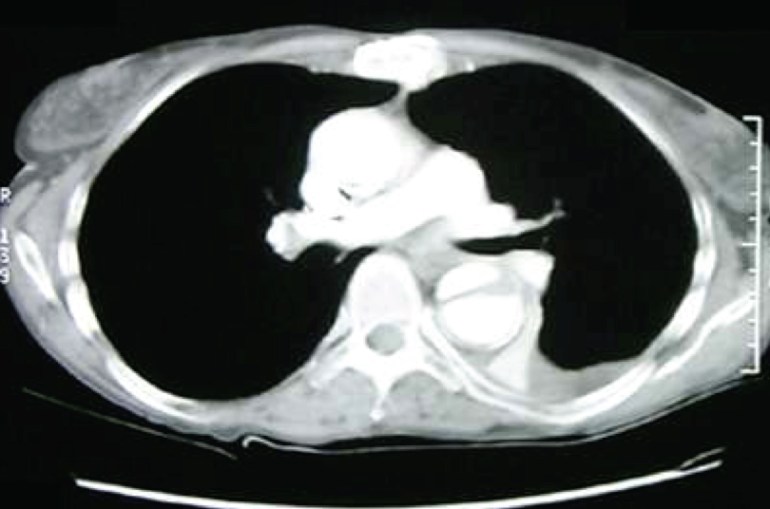

A rather difficult case to guess, perhaps. But this patient had a normal WBC with normal differential counts despite having Gram-negative bacteraemia, and one of the few types of Gram-negative rods where such a phenomenon is observed is Salmonella spp. Given the elderly patient and the aortic dissection seen on the chest X-ray, this is likely non-typhoidal Salmonella bacteraemia with infected aortic aneurysm/dissection. A CT image is shown below.